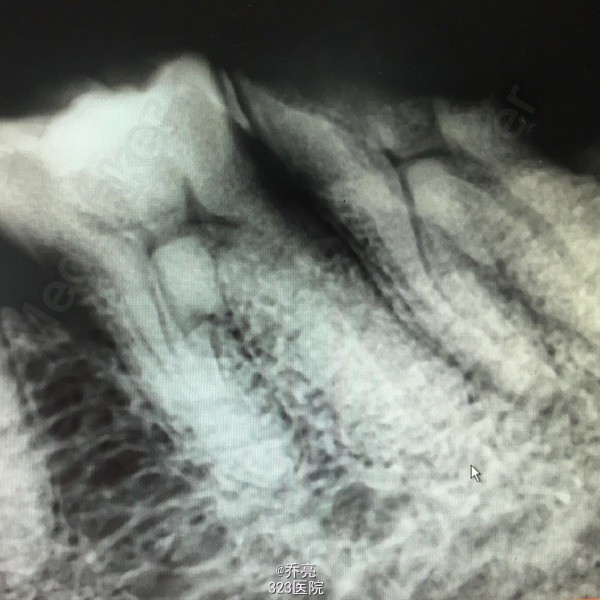

左下后牙金属牙冠松动,牙齿咬物不适一个月

左下7金属牙冠松动,不密合,去除后牙体缺损,面积较大,探(+)冷(+)松动1度,叩(+-) 右上1松动2度 x线示:左下7缺损及髓,根尖无明显异常 右上1根尖阴影

诊断:左下7慢性牙髓炎 右上1牙槽骨吸收 建议:左下7RCT+桩+冠 右上1抜除后修复 处理:左下7清理根管,双氧水冲洗,干燥置木溜油棉,ZOE暂封 右上1局麻下拔除,牙槽窝搔刮,恢复牙槽窝,咬干棉球止血